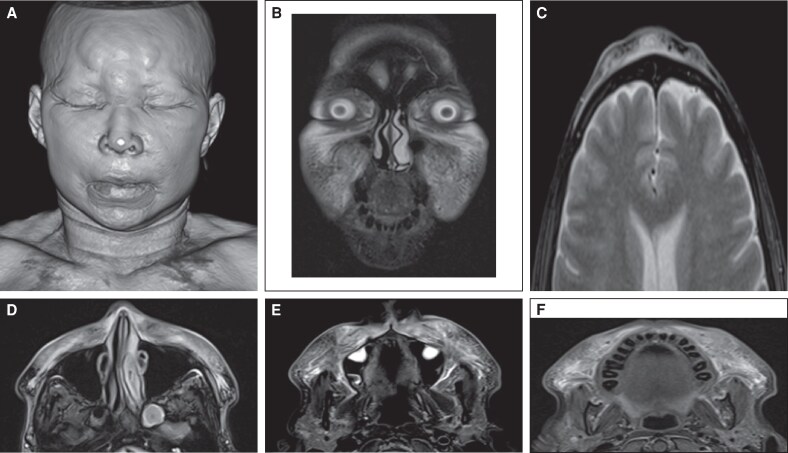

生物聚合物经常用于美学或重建目的,通常没有充分考虑它们可能引起的潜在的长期健康并发症。这些物质的使用与佐剂诱导的自身免疫/自身炎症综合征(ASIA综合征)有关;然而,现有文献有限,目前对其管理尚无明确的共识。本病例报告旨在描述一个诊断为类风湿关节炎的患者中严重的生物聚合物诱导炎症性疾病的病例,强调诊断和治疗方法。本病例报告检查了一名58岁女性患者,20年前曾在臀部和面部区域应用生物聚合物,过去2年诊断为类风湿关节炎。她表现为严重的炎症性皮肤病变,伴有关节痛的恶化。MRI扫描显示外源性物质伴周围组织严重炎症征象,活检符合“瑞士奶酪”形态的异物肉芽肿。患者住院并接受多学科治疗,取得了良好的临床疗效。本病例强调了对自身免疫性疾病和既往接触过生物聚合物的患者进行综合评估和多学科方法的重要性。自身免疫性疾病的共存可加重炎症反应,提示需要进一步研究这种相互作用及其预后影响。证据等级:5(风险)。

Biopolymers are frequently used for aesthetic or reconstructive purposes, often without adequate consideration of the potential long-term health complications they may cause. The use of these substances has been associated with autoimmune/autoinflammatory syndrome induced by adjuvants (ASIA syndrome); however, the existing literature is limited, and there is currently no clear consensus regarding its management. This case report aims to describe a case of severe biopolymer-induced inflammatory disease in a patient with a diagnosis of rheumatoid arthritis, highlighting both the diagnostic and therapeutic approaches. This case report examines a 58-year-old female patient with a history of biopolymer application to the gluteal and facial region 20 years before and a diagnosis of rheumatoid arthritis for the past 2 years. She presented with severe inflammatory skin lesions with worsening arthralgia. An MRI scan revealed exogenous material with signs of severe inflammation of the surrounding tissues, and a biopsy was consistent with foreign body granulomas with a "Swiss cheese" morphology. The patient was hospitalized and received multidisciplinary management, achieving an excellent clinical response. This case highlights the importance of a comprehensive evaluation and a multidisciplinary approach in patients with autoimmune disease and previous exposure to biopolymers. The coexistence of autoimmune diseases can aggravate the inflammatory response, suggesting the need for additional studies exploring this interaction and its prognostic impact. Level of Evidence: 5 (Risk).